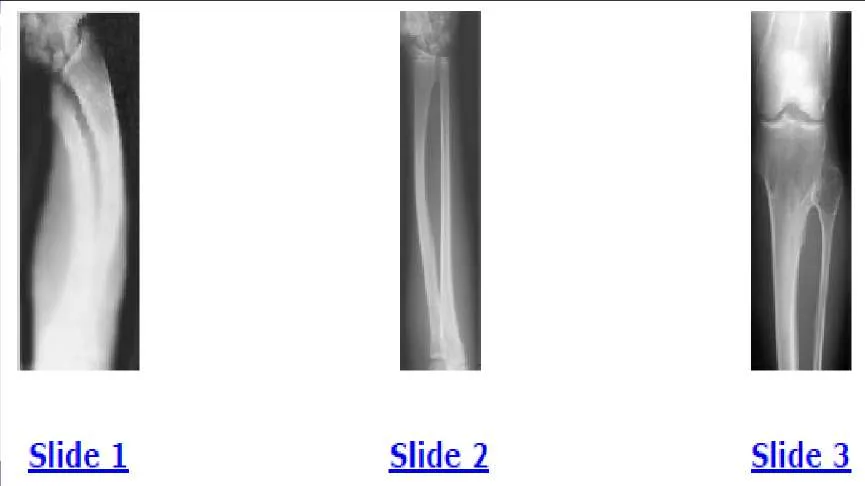

A 12-year-old boy is brought to the clinic by his concerned parents. The boyâ s forearm is bowed, and his parents are confused as to the possible diagnosis and treatment options. You notice that the right forearm of the child is bowed ulnarwards and is shorter compared to the left forearm. The pronosupination is markedly decreased on the right side but is also limited on the left side. The patient has a good grip, pinch, and grasp. He is neurologically intact as well. The parents say that they first noticed the deformity around 6 or 7 years ago, and the mother informs you that she had noticed a hard bump on the forearm. She has recently noticed another bump on his right leg. The child does not complain of pain and is using both of his hands quite well. The parents were informed by a previous physician that the child has Madelungâ s deformity and are concerned that the disease is now involving other areas of his body. You order a radiograph of the patientâ s forearm. The anteroposterior radiograph is shown (Slide). The next step is to order a:

Correct Answer: Skeletal radiograph survey

Explanation:

A 12-year-old boy is brought to the clinic by his concerned parents. The boyâ s forearm is bowed, and his parents are confused as to the possible diagnosis and treatment options. You notice that the right forearm of the child is bowed ulnarwards and is shorter compared to the left forearm. The pronosupination is markedly decreased on the right side but is also limited on the left side. The patient has a good grip, pinch, and grasp. He is neurologically intact as well. The parents say that they first noticed the deformity around 6 or 7 years ago, and the mother informs you that she had noticed a hard bump on the forearm. She has recently noticed another bump on his right leg. The child does not complain of pain and is using both of his hands quite well. The parents were informed by a previous physician that the child has Madelungs deformity and are concerned that the disease is now involving other areas of his body. An immediate appointment for magnetic resonance imagine (MRI) and computed tomography (C T) scan are not available, and a genetic evaluation has been carried out previously. As you await the report from the geneticist office, you decide to get a skeletal radiograph series on the patient. The radiograph of the opposite forearm (Slide 1) and right leg are shown (Slide 2). You order a radiograph of the forearm. The anteroposterior radiograph is shown (Slide 3). Your suspected diagnosis is:

Correct Answer: Diaphyseal achalasia

Diaphyseal achalasia, also called multiple hereditary exostoses, classically presents in a young individual with multiple sites of involvement. The more involved the disease, the more likely hand involvement becomes. Forearm involvement is also common. The radius is bowed due to the shortened ulna. The risk of radial head dislocation is higher if the radius does not bow. While infection or traumatic injury could have produced early physeal arrest as seen in the first radiograph, presence of lesions elsewhere indicates multiple hereditary exostoses and should be investigated with skeletal surveys. Multiple epiphyseal dysplasia is not a possible diagnosis as only the ulna is involved in the first radiograph and radius alone in the left forearm. No enchondromas are present.

A 12-year-old boy is brought to the clinic by his concerned parents. The boys forearm is bowed, and his parents are confused as to the possible diagnosis and treatment options. You notice that the right forearm of the child is bowed ulnarwards and is shorter compared to the left forearm. The pronosupination is markedly decreased on the right side but is also limited on the left side. The patient has a good grip, pinch, and grasp. He is neurologically intact as well. The parents say that they first noticed the deformity around 6 or 7 years ago, and the mother informs you that she had noticed a hard bump on the forearm. She has recently noticed another bump on his right leg. The child does not complain of pain and is using both of his hands quite well. The parents were informed by a previous physician that the child has Madelungs deformity and are concerned that the disease is now involving other areas of his body. You order a radiograph of the forearm. The anteroposterior radiograph is shown (Slide 1). The childâ s skeletal radiograph survey is also presented (Slide 2 and Slide 3). The genetic pattern seen in patients with this type of presentation is:

Correct Answer: Autosomal dominant

Multiple hereditary exostoses is inherited in an autosomal-dominant manner with 90% penetrance.